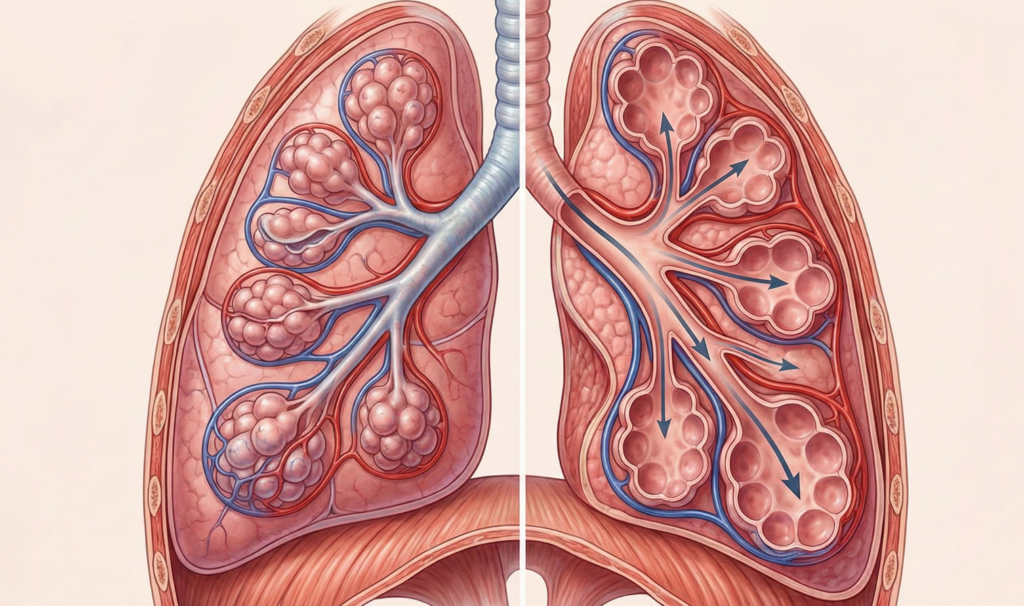

O que acontece nos pulmões quando você suspira?

Durante a respiração comum, alguns alvéolos pulmonares podem se fechar parcialmente. O suspiro força sua reabertura, garantindo trocas gasosas eficientes e evitando a queda de oxigênio.

Esse processo melhora a função pulmonar e impede o acúmulo de dióxido de carbono. É por isso que o corpo usa o suspiro como manutenção automática, mesmo quando você não percebe.